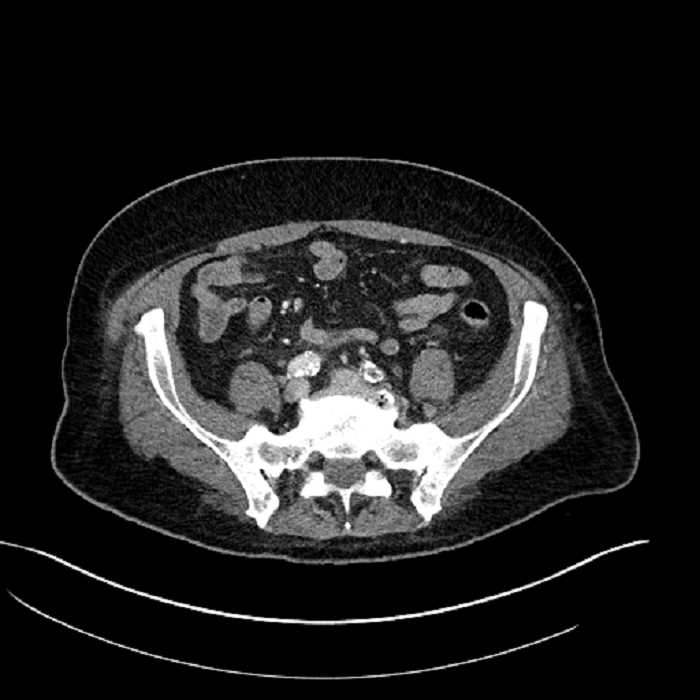

• Mild mural thickening of a segment of the sigmoid colon with adjacent fat stranding and a 1.5 cm fluid and gas collection along the tip of an inflamed diverticulum

• Loss of the normal fat plane between this collection and adjacent loops of small bowel, which demonstrate mural thickening

• No bowel obstruction

Acute sigmoid diverticulitis complicated by a small contained perforation and a large abscess in the right hepatic lobe. Additional small subcapsular abscesses along the anterior margin of the left hepatic lobe.

Additionally, loss of the normal fat plane between the peridiverticular collection and adjacent thickened loops of small bowel raises the potential for an enterocolonic fistula.

Hepatic abscess showing the double target sign with low density internally surrounded by a thin inner enhancing rim (red arrow) and ill-defined outer low density rim (yellow arrow). Blue arrow indicates an internal septation. Red arrows: additional smaller subcapsular abscesses. Red arrow: focal contained perforation associated with diverticulitis.